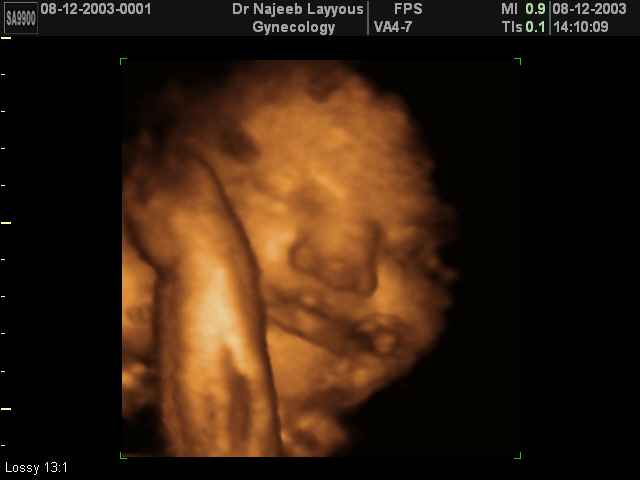

3D Fetal Face Ultrasound Scan Photos